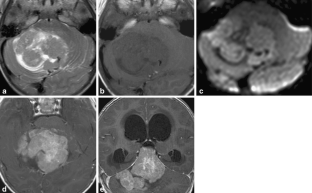

Magnetic resonance imaging spectrum of medulloblastoma

Two medulloblastoma variants were recently added to the WHO classification of CNS tumours. We retrospectively analysed the imaging findings of 37 classic and 27 cases of variant medulloblastomas to identify imaging characteristics that might suggest a particular MB subtype.

Sixty-four patients from three institutions were included. Location, tumour margins, signal intensities on conventional MRI, enhancement pattern, the presence of haemorrhage, calcifications and hydrocephalus were recorded and analysed. Signal characteristics on diffusion-weighted MR images and MR spectra were evaluated when available.

Thirty-seven classic type of MB (CMB), twelve cases of desmoplastic/nodular medulloblastoma (DMB), nine medulloblastomas with extensive nodularity (MB-EN), five cases of anaplastic and one of large-cell medulloblastoma were included. Fifty of 64 tumours were located in the 4th ventricle region. On T2WI, CMB were all hyperintense, whereas DMB and MB-EN showed isointensity in up to 66%. One third of the classic MB showed only subtle marginal or linear enhancement. All medulloblastoma variants showed marked enhancement.

The results of our study suggest: (a) an age-dependent distribution of MB variants, with DMB and MB-EN more common in younger children; (b) a female predominance in DMB; (c) a more common off-midline location in DMB (50%) and MB-EN (33%) variants.

Fig. 2